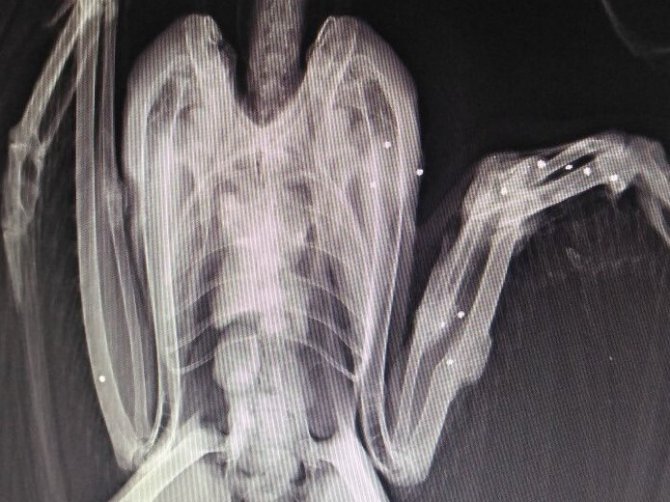

Tarım ve Orman Bakanlığı Doğa Koruma ve Milli Parklar (DKMP) 10. Bölge Müdürlüğü'ne bağlı Sinop Sarıkum Yaban Hayatı Kurtarma ve Rehabilitasyon Merkezi'nde ateşli silahla veya farklı doğal sebeplerle yaralanan, hasta, doğada aç kalmış yaban hayvanları rehabilitasyona alınarak gerekli tedavileri sağlanıyor. İyi ve sağlıklı duruma getirilen hayvanlar ise yeniden doğal yaşam alanına salınıyor. DKMP 10. Bölge Müdürlüğü bünyesinde Sinop, Kastamonu, Bartın, Karabük ve Zonguldak'ta hizmet veren merkez, ihtiyaç duyulması halinde diğer farklı illerden gelen yaban hayvanlarına da ev sahipliği yapıyor.

Sinop Sarıkum Yaban Hayatı Kurtarma ve Rehabilitasyon Merkezi'nde 2022 yılında, doğada çeşitli sebeplerle yaralanmış 329 yaban hayvanı tedavi altına alındığı ve bunların 224'ünün tekrar sağlığına kavuşarak doğal ortamlarına salındığı kaydedildi.

"Aralarında ağaç sansarı, ala doğan, alaca ağaçkakan, alaca baykuş, Anadolu sincabı, angıt, arı şahini, atmaca, bahri, balaban, bıldırcın, bıldırcın kılavuzu, boz ayı, çakal, çeltikçi, çıkrıkçın, çobanaldatan, ebabil, ekin kargası, erguvani balıkçıl, ev kırlangıcı, gri balıkçıl, guguk, gümüş martı, ibibik, ishakkuşu, karaca, karagerdanlı dalgıç, karatavuk, kaya güvercini, kaya kartalı, kızıl şahin, kukumav, kulaklı orman baykuşu, kumru, küçük akbaba, küçük balaban, leş kargası, leylek, öter ardıç, peçeli baykuş, puhu, bayağı puhu, serçe, su kılavuzu, su samuru, su tavuğu, şahin, bayağı şahin, taşçeviren, tilki, tosbağa, turna, vaşak, yabani tavşan ile yediuyur türleri."